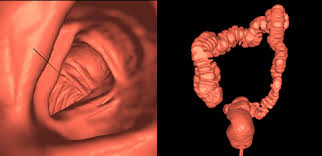

5. 영상재구성 알고리즘의 새로운 개발은 3-Dimensional 영상기법을 이용한 내시경적 검사를 대신하여  CT 영상으로 나타낼 수 있게 되었다.

출처: Xlab Medic

(실제 내시경을 하지 않았지만 얻은 데이터를 바탕으로 마치 내시경을 하는 것처럼 혈관, 대장 등의 속을 들여다볼 수 있습니다.)